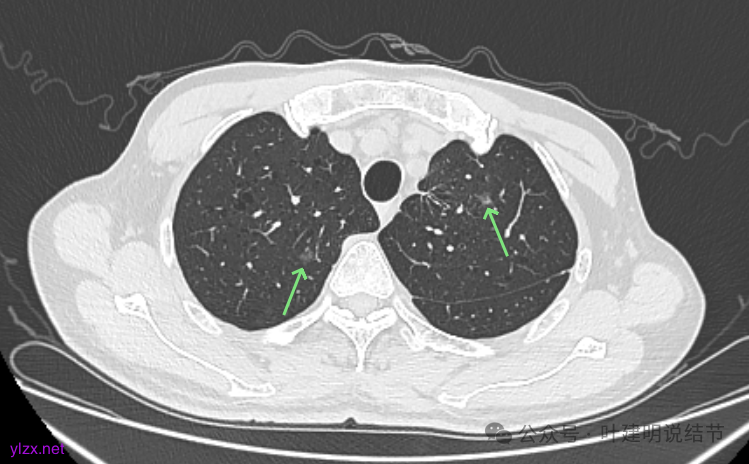

右上冠状位显示病灶纯磨,血管进入穿行,灶内空泡征,表面毛刺征,没有明显实性成分。

左上病灶冠状位显示纯磨,部分连续细毛刺,灶内有扩张的细支气管似的,整体轮廓清。

矢状位见右上病灶也是纯磨,灶内的血管可见,表面部分有细毛刺,整体轮廓与边界清楚。

左上病灶矢状位见也是纯的,没有实性成分。